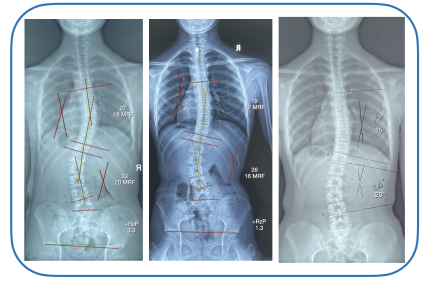

Cases of Scoliosis Treatment in Singapore

Case 1

Case 2

Case 3

Case 4

Case 5